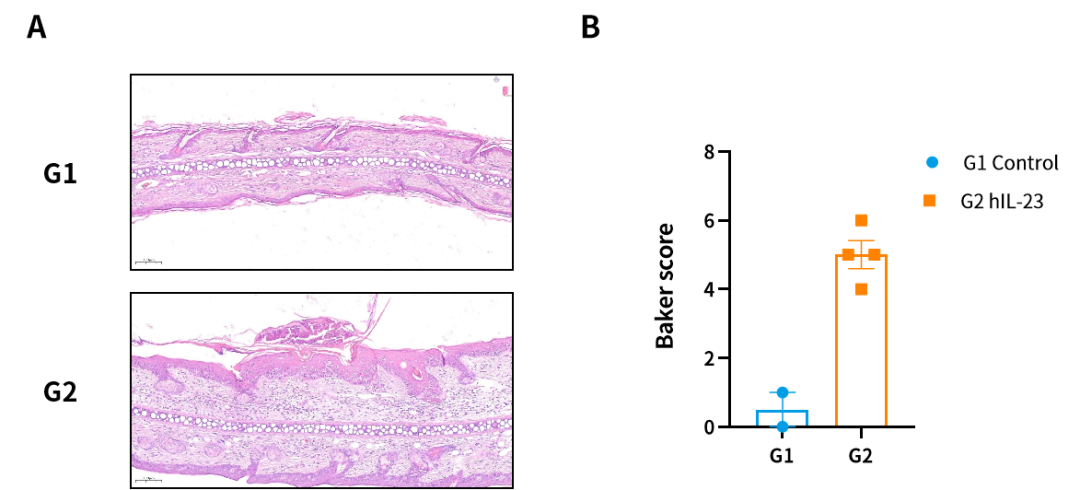

图8. Human IL-23因子诱导的大鼠银屑病模型。(A)H&E染色代表图;(B)Baker评分。